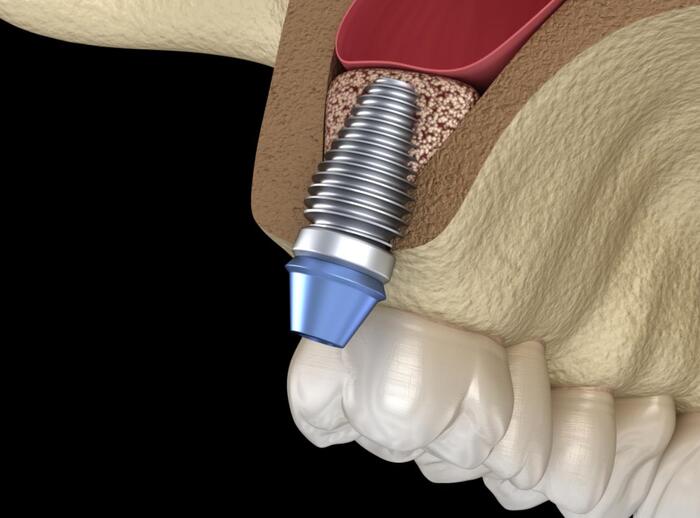

Ghép xương nâng xoang (nâng xoang hàm hay ghép xương xoang hàm) là thủ thuật nha khoa nhằm tăng thể tích xương ở vùng hàm trên chuẩn bị cho việc cấy ghép Implant.

Ghép xương nâng xoang là phương án thường được thực hiện trước khi tiến hành trồng răng Implant. Đây là kĩ thuật đặt xương nhân tạo hoặc xương tự thân vào giữa màng xoang và bề mặt xương vùng đáy xoang hàm. Điều này giúp tăng khối lượng xương và đủ vị trí cho chân răng Implant.

Xoang hàm trên nằm ở vùng hàm trên phía sau, giữa đầu và mũi, từ răng số 4 đến số 8. Đây là xoang lớn nhất nên việc nâng đáy xoang hàm lên nhằm tăng chiều cao xương lên phía trên, đặc biệt khu vực răng số 6,7.

Cấy ghép Implant là hình thức đặt trụ Implant trực tiếp vào xương hàm, thay thế cho chân răng đã mất. Trồng răng Implant thành công phụ thuộc vào mật độ, thể tích xương, chiều cao đủ tốt để bao bọc, nâng đỡ trụ. Với các trường hợp tiêu xương nặng, thoái hóa xương hàm thì việc nâng xoang là cần thiết vì:

- Nâng xoang đảm bảo độ dài trụ sau khi cấy không làm tổn thương xương hàm, giúp trụ đứng vững.